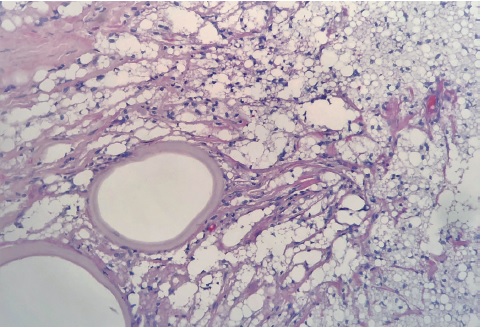

Em março de 2006, a paciente voltou à consulta, relatando o surgimento de nódulo endurecido e doloroso, de 7cm, na face lateral da coxa esquerda há um ano. Após avaliação ultrassonográfica, que descreveu formações ecogênicas de limites imprecisos no subcutâneo da face e xterna da coxa esquerda, região inguinal esquerda e face interna da coxa direita, foi colhida biópsia incisional de lesão, cujo estudo anatomopatológico revelou tumor lipomatoso atípico, com pesquisa negativa para germes comuns, fungos e micobactérias. Em fevereiro de 2012, a exérese dessa lesão (Figura 2) revelou extensa esteatonecrose ao exame histopatológico. A ressonância magnética realizada após a cirurgia evidenciou, além de múltiplos linfonodos de aspecto inespecífico nas cadeias ilíacas e femorais, infiltração líquida no subcutâneo da região glútea (Figura 3).

Considerando a esteatonecrose, achado presente à histopatologia de algumas paniculites lobulares, a imagem de infiltração líquida na região glútea e a revisão da história clínica (informação da paciente de injeção de silicone em regiões glúteas pelo menos 10 anos antes da admissão), aventou-se a possibilidade de paniculite factícia por substância exógena.